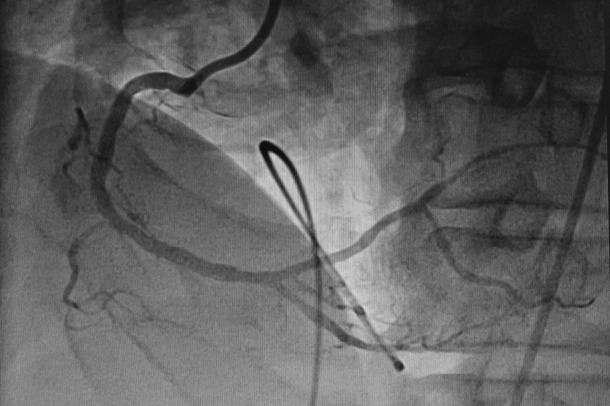

Development of coronary artery aneurysm (CAA) after implantation of drug-eluting stent is occasionally observed. We present a case of a 67-year-old man who underwent everolimus-eluting stent (EES) implantation in right coronary artery (RCA) for inferior wall myocardial infarction, and thereafter, giant CAAs were developed in the vessel of stent deployment, within 2 months. However, the patient was managed with coronary artery bypass grafting (CABG). On follow-up, the patient's condition was stable. To the best of our knowledge, we report the first case of occurrence of EES-associated giant CAAs in RCA subsequently treated with CABG.

摘要

药物洗脱支架植入后偶尔会观察到冠状动脉瘤(CAA)的发生。我们报告一例67岁男性患者,其因下壁心肌梗死在右冠状动脉(RCA)植入依维莫司洗脱支架(EES),此后在支架置入血管内2个月内出现巨大CAA。然而,该患者接受了冠状动脉旁路移植术(CABG)治疗。随访时,患者病情稳定。据我们所知,我们报告了首例RCA中发生EES相关巨大CAA并随后接受CABG治疗的病例。